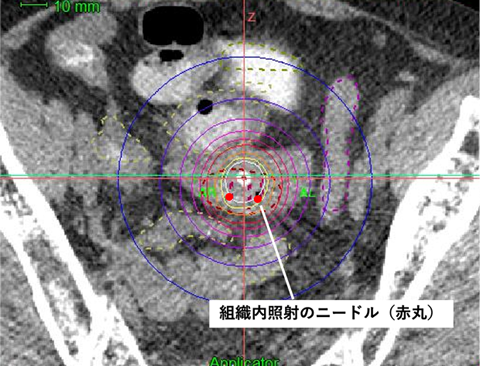

組織内照射とは、腫瘍の内部やその周囲に専用の細いニードル(径約2mm)をCT画像誘導下に直接刺入し、そのニードルを通して放射線を照射する治療法です。

近年、通常の腔内照射に組織内照射を併用するハイブリッド腔内照射と呼ばれる照射方法が普及してきています。

当院は県内で唯一、このハイブリッド腔内照射を施行可能な施設です。

従来の治療法が困難とされる症例にも放射線をより効果的に照射することが期待されています。